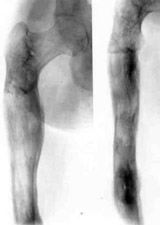

Replacement of nonviable tissues of lower/third of hip with elongation of hip by means of Ilisarov's apparatus.Replacement of nonviable tissues of lower/third of hip with elongation of hip by means of Ilisarov's apparatus.

Replacement of nonviable tissues of lower/third of hip with elongation of hip by means of Ilisarov's apparatus.